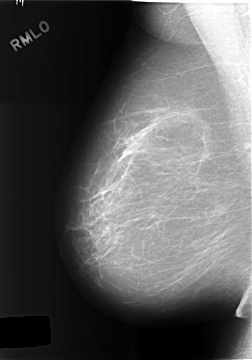

C_0469_1.RIGHT_MLO

RIGHT_CC LINES 5736 PIXELS_PER_LINE 4064 BITS_PER_PIXEL 12 RESOLUTION 50 NON_OVERLAY

RIGHT_MLO LINES 5760 PIXELS_PER_LINE 4024 BITS_PER_PIXEL 12 RESOLUTION 50 NON_OVERLAY